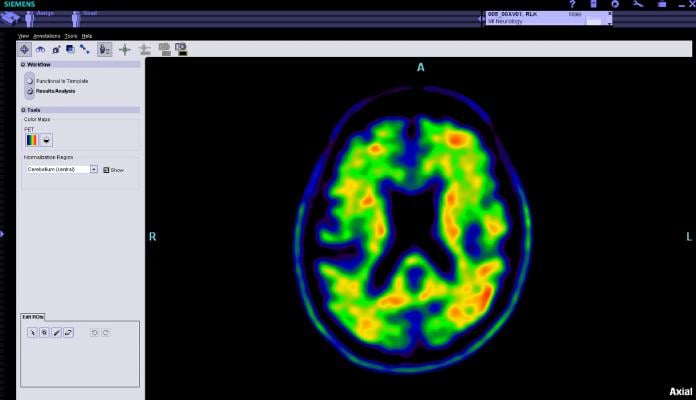

Two abnormal structures called plaques and tangles are prime suspects in damaging and killing nerve cells in Alzheimer's. The plaques are deposits of a protein fragment called amyloid-beta that build up in the spaces between nerve cells. Amyloid PET imaging represents a potential major advance in the clinical assessment of people with cognitive impairment. The technology makes amyloid plaques light up on a brain PET scan, enabling for the first time accurate detection of plaques in living people.

"The purpose of the IDEAS Study is to examine how brain imaging, specifically an amyloid PET scan, helps guide doctors in diagnosing and treating Alzheimer's and other dementias in cases where the cause of cognitive impairment is difficult to diagnose," said Gil D. Rabinovici, M.D., IDEAS Study chair and associate professor of neurology at the University of California, San Francisco. "We believe the study will show that, in diagnostically uncertain cases, knowledge of amyloid status will lead to significant changes in patient management — such as earlier counseling and prescription of more appropriate drugs — that will translate into improved long-term outcomes."

Amyloid PET imaging alone does not establish a diagnosis of Alzheimer's disease, but must be considered in the context of the person's medical history, physical examination and cognitive testing. To guide clinicians on how best to apply amyloid PET in the clinical evaluation of people with cognitive decline, a working group convened by the Alzheimer's Association and the Society of Nuclear Medicine and Molecular Imaging (SNMMI) developed appropriate use criteria (AUC) for brain amyloid PET scans.

The AUC indicate that amyloid PET should only be considered in patients with clear, measurable cognitive deficits when there is substantial diagnostic uncertainty after a comprehensive evaluation by a dementia specialist. According to AUC, amyloid PET may have greatest value in patients with either: (1) progressive, unexplained mild cognitive impairment (MCI); or (2) dementia of uncertain cause due to atypical or mixed symptoms, or unusually early age-of-onset.